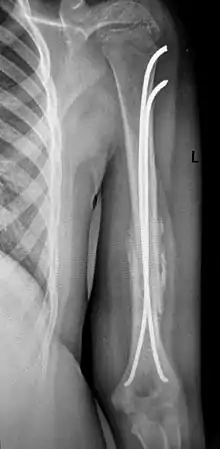

Хирургическое лечение также показано при многооскольчатых переломах плеча, невозможности закрытой репозиции, интерпозиции мягких тканей и повреждении сосудов и нервов. Фиксацию отломков осуществляют при помощи пластин, интрамедуллярных штифтов с блокированием, или аппарата Илизарова.